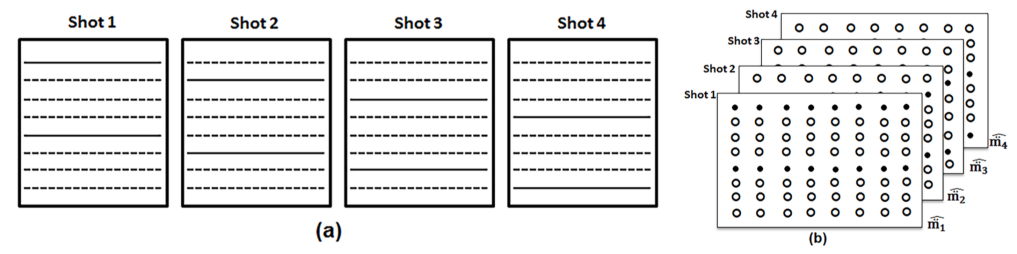

In an -shot EPI-based sensitivity-encoded diffusion acquisition for sampling an imaging matrix, the readout is shortened by collecting only phase encoding lines during every acquisition. The acquisition is repeated times, each time sequentially collecting the next set of phase-encoding lines (see figure 1(a) for a cartoon of a 4-shot acquisition). In figure 1(b), we represent the 4-shot acquisition using four k-space data matrices concatenated along the shot dimension. The acquired k-space samples are marked using solid circles and the unacquired k-space samples are marked using hollow circles. Note that if phase differences due to inter-shot motion are absent, then we can fill a single k-space data matrix with the sampled points occupying the appropriate positions in the data matrix. In fact, this method is often used in the recovery of the non-diffusion weighted images collected as part of the MS-DWI acquisition. During a diffusion-weighted acquisition, the diffusion sensitizing gradients add extra phase to the moving spins and the acquired k-space data for each shot will have a different phase due to the shot-to-shot inherent sub-pixel motion of the imaging sample. Hence, the acquired k-space data from the separate shots cannot be combined directly; instead they are stacked into separate matrices. Our aim is to recover the unaliased k-space data samples in each of the four k-space data matrices based on the samples that we collected.

Fig 1: (a) A 4-shot acquisition illustrated. (b) The k-space data matrix of the 4-shot DWI acquisition. The solid circles and the hollow circles represent the acquired and unacquired k-space samples during each shot respectively.